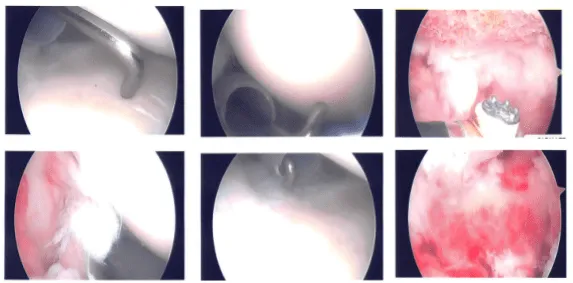

The posterior entry portal was made, which was a soft spot. Arthroscope was entered into the glenohumeral ligament. Anterosuperior portal was also made with the use of Shaver and was introduced from the anterosuperior portal.

There was fraying of the glenoid labrum as well as articular site of the rotator cuff, which were debrided with the use of shaver. There was also partial tearing and fraying of the subscapularis tendon, which was also cleaned with the shaver.

There was no damage. Pictures were taken and saved. The arthroscope was entered into subacromial space. There was subacromial bursitis, which was debrided. There was bleeding and difficulty due to the patient’s weight and size.

Coblation wand was used followed by burr to perform acromioplasty of the right shoulder. Distal clavicle excision was also done with the use of Coblation wand and #6-0 burr. Rotator cuff was not done on the bursal site; so, a decision was made to open the rotator cuff with the use of a Regeneten implant.

Large Regeneten implant was introduced through the lateral portal and was put in place with the use of PLA tacks x8. Final pictures were taken and saved. The shoulder was thoroughly irrigated and drained.

Intraoperative photo